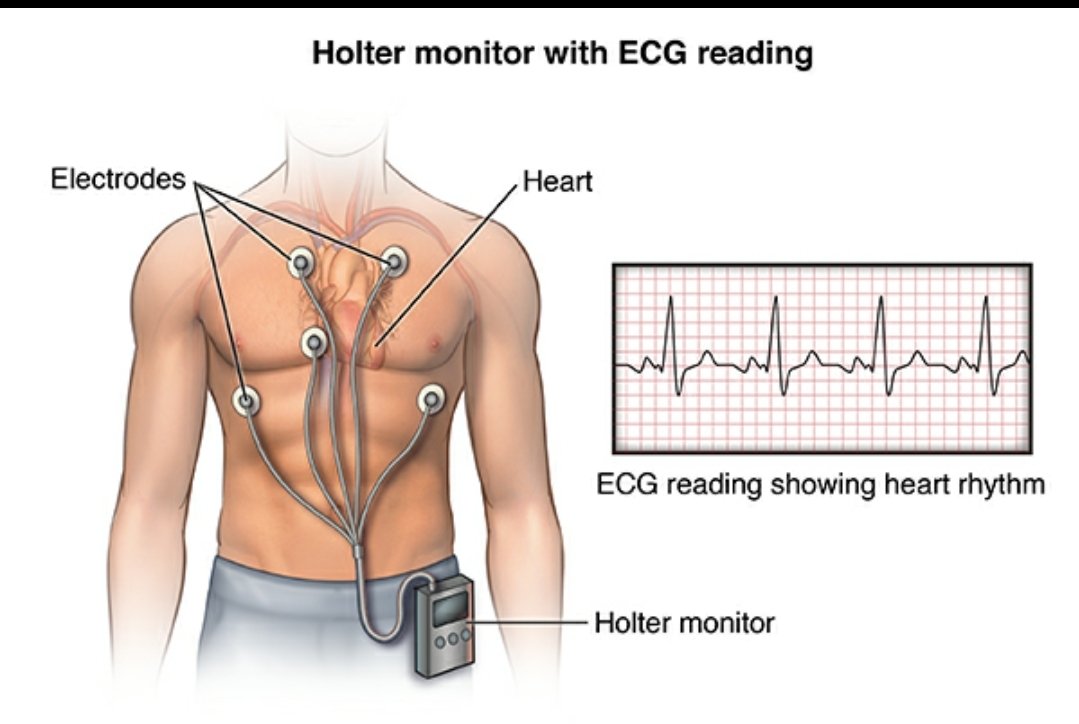

🧠أمراض القلب

❤ارتجاف اذيني❤تخثرات

🧠أمراض القلب

❤ارتجاف اذيني❤تخثرات

🧠فحوصات للقلب

♦️تخطيط عادي/مطول

♦️اشعه صوتيهECHOمباشرة/بمنظار

🧠فحوصات للقلب

♦️تخطيط عادي/مطول

♦️اشعه صوتيهECHOمباشرة/بمنظار